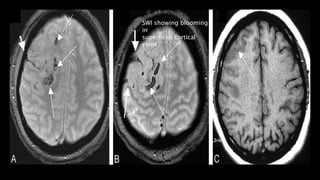

•T2* (GRE, SWI) key to diagnosis

○ "Blooming" thrombus in vein(s)

SWI showing blooming

in

superficial cortical

veins

in right VOT

T1WI

showing

linear

hyperintensi

ty

• #145 Here is a c/o superficial venous thrombosis. T2* GRE image shows lineaer hypointensity in right paracentral sulcus ( short arrow)due to magnatic succeptility effect at the site of thrombosed vein. Hypointense area shows corresponding AREAS OF cortical hemorrhage ( long arrow). On T1 wi only swollen gyri are seen.

• #146 This is a c/o VOT thrombosis.Axial T1wi Mri BRAIN shows T1 hyperintensity in post central gyrus , typical site for VOT s/o thrombosis and SWI shows blooming in the region of thrombosed vdein